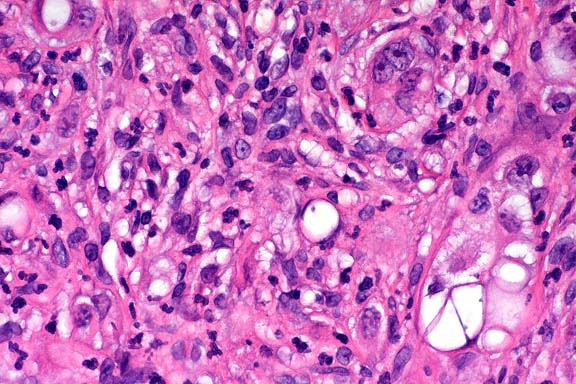

- Contributor's Diagnosis and Comments: Liver: Multifocal necrotizing

hepatitis with syncytial giant cells.

Etiology: Mouse hepatitis virus (MHV).

- Death is generally not associated with MHV infection except

when the infection occurs in immunocompromised mice. Syncytial

cells are commonly seen in murine coronavirus infection. A diagnosis

of MHV is based on the liver lesions with syncytial giant cells

and the serological analysis of the room sentinel mice.

10x

obj

- Case 15-4. Liver. Severe focal to coalescing necrosis

is associated with inflammatory cell infiltration and syncytial

giant cells.

40x

- Case 15-4. Liver. Areas of hepatocellular necrosis

are replaced by necrotic cellular debris, hemorrhage, neutrophils

and occasional clusters of nuclei (hepatocyte syncytium). An

adjacent hepatic vein contains endothelial cell hypertrophy and

hyperplasia.

- AFIP Diagnosis: Liver: Necrosis, random, multifocal

to coalescing, with syncytia and mild neutrophilic inflammation,

CBA/CaJ mouse, rodent.